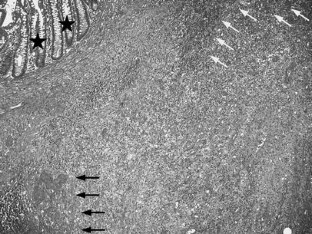

Fig. 1.

Fig. 2a, b.

Fig. 3.